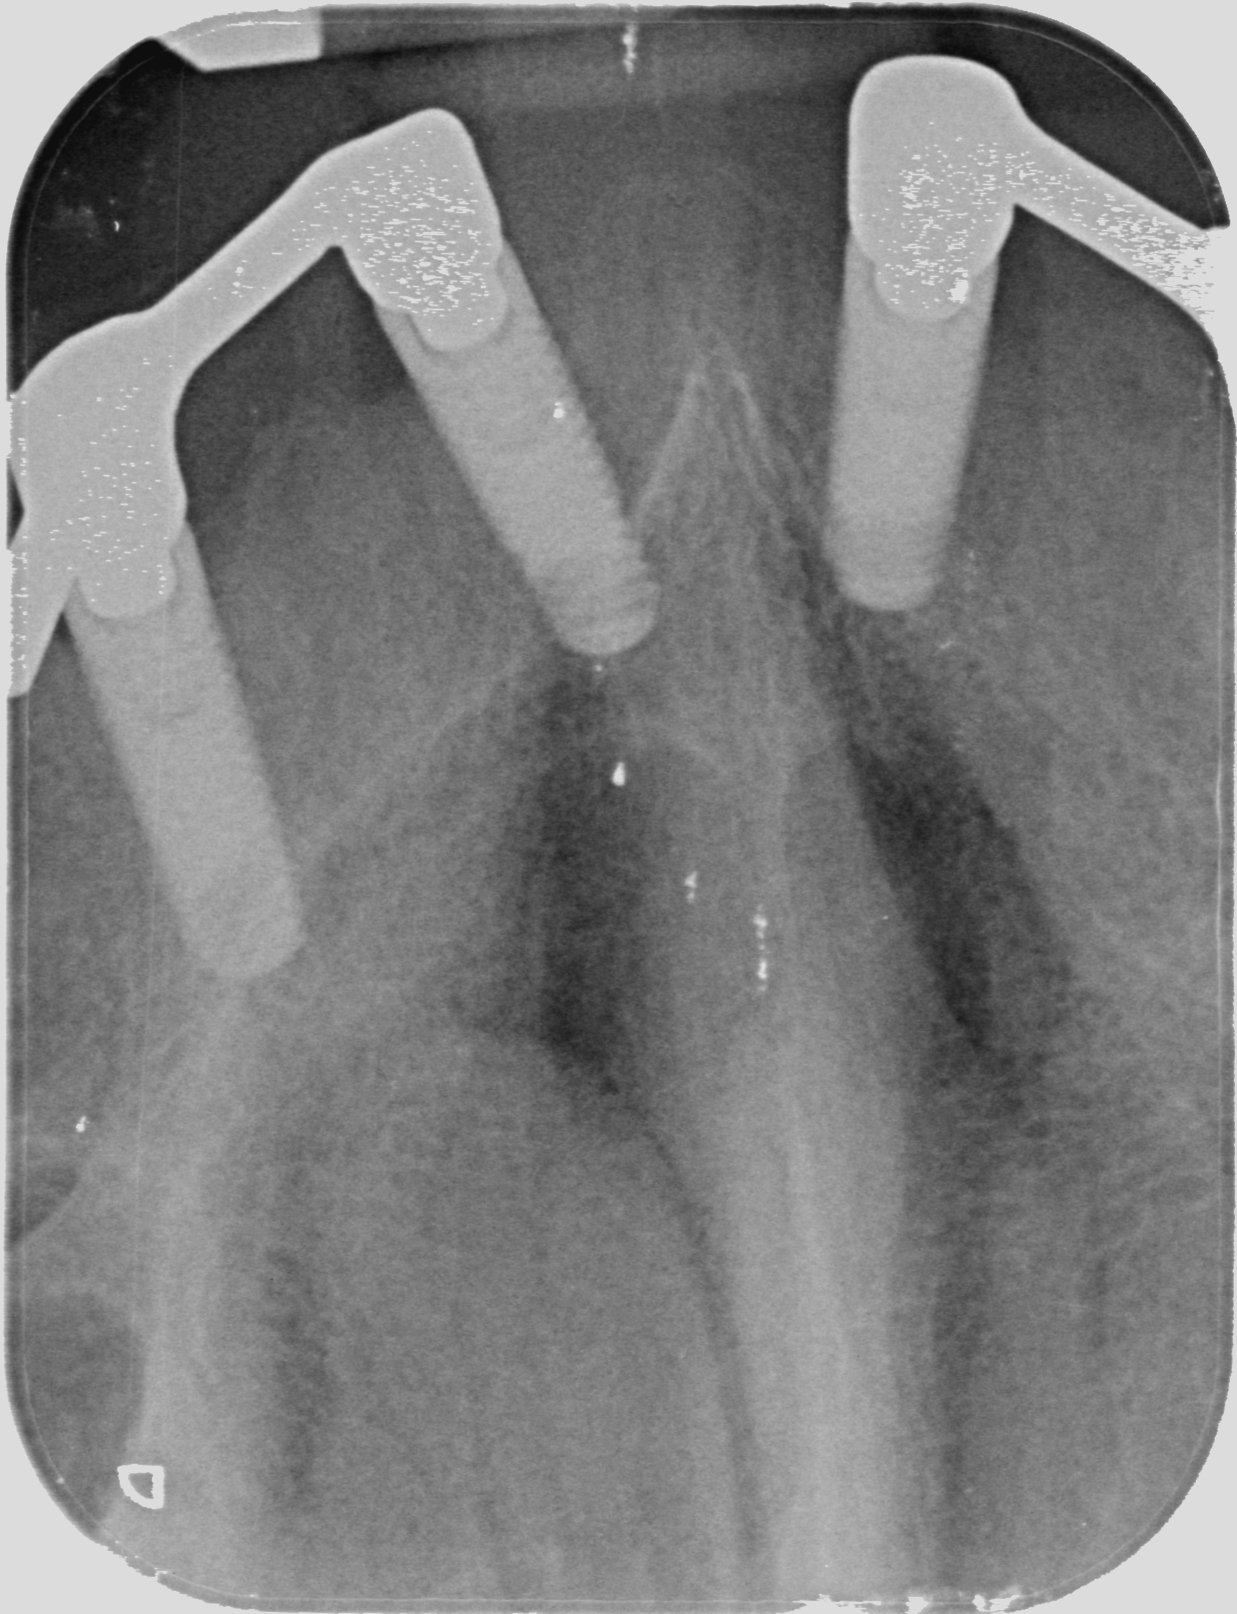

Buenos días: Tengo una paciente con implantes colocados en el 2003 en una clínica que ha desaparecido y no sabemos ni la marca ni la medida.Necesito levantar la prótesis y [...]

Queremos cambiar prótesis aprovechando los implantes

paciente proviniente de otra consulta ya cerrada ( por fallecimiento del titular ) imposible obtener datos de historia clìnica . Varios van al cubo pero al menos dos intentaremos recuperar [...]